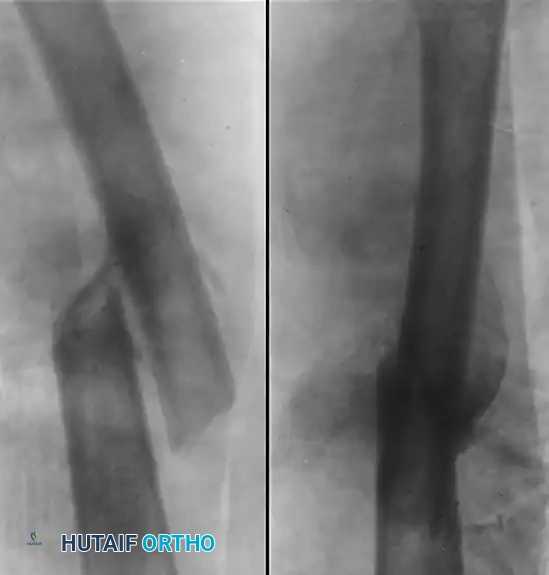

The following imaging demonstrates the natural history and surgical management of a severe pediatric femoral malunion.

Figure A: Demonstrates a severely malunited fracture of the femur with significant overlapping of fragments and angular deformity in an 11-year-old boy. At this degree of shortening and angulation, spontaneous remodeling alone is insufficient to restore normal biomechanics.